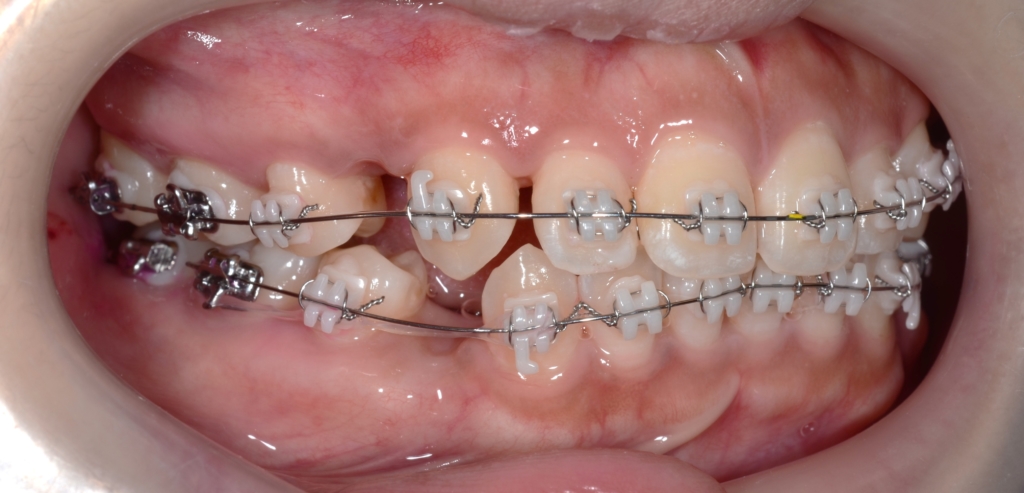

順調にステップが進み、前歯を最大限に引っ込めるステップに入りました。

【上の歯列の更なる後方への移動を図る】

隙間分はしっかり引っ込めたのですが、元の噛み合わせが上顎前突傾向でしたので、出っ歯が残ってしまいました。 そこで、より引っ込んだ下の歯列に上の歯列を引っ込めて合わせるという次のステップに進めることにしました。

あらためて、上顎にアンカースクリューを植立しました。

アンカースクリューを用いて矯正力を加えることで、上顎歯列全体を後方へ移動させて、口元の見た目の更なる改善を図ります。

同じことをしている方の写真をイメージ写真としてあげています。